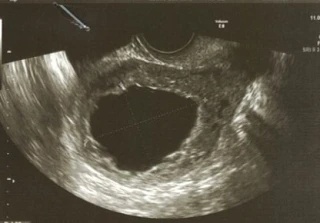

Московские врачи спасли беременную с редкой и опасной локализацией плодного яйца

Врачи Национального медицинского исследовательского центра акушерства, гинекологии и перинатологии имени академика В. И. Кулакова Минздрава России спасли жизнь пациентке с интрамуральной беременностью. При такой редкой и опасной патологии плодное яйцо находится не в полости матки и не в маточных трубах, а в толще миометрия, что делает течение беременности нестабильным и рискованным, сообщила

Врачи Национального медицинского исследовательского центра акушерства, гинекологии и перинатологии имени академика В. И. Кулакова Минздрава России спасли жизнь пациентке с интрамуральной беременностью. При такой редкой и опасной патологии плодное яйцо находится не в полости матки и не в маточных трубах, а в толще миометрия, что делает течение беременности нестабильным и рискованным, сообщила пресс-служба учреждения.

— Два года назад у женщины на этапе подготовки к ЭКО было выявлено злокачественное заболевание слепой кишки; она успешно прошла лечение и вышла в ремиссию. Теперь было диагностировано подозрительное кистозное образование величиной более двух сантиметров, поэтому женщину направили на оперативное вмешательство в наше отделение, — рассказала акушер‑гинеколог, онколог отделения Полина Шешко. — Лапароскопически мы удалили опухоль и отправили на гистологическое исследование, которое выявило хориальную ткань. Она формируется на ранних сроках беременности и становится основой для развития плаценты. Так, опухоль оказалась плодным яйцом, которое закрепилось в мышечном слое матки.

По словам врачей, нетипичная локализация плодного яйца существенно повышает риск серьёзных осложнений — например, разрыва миометрия с массивным внутренним кровотечением. В тяжёлых случаях может потребоваться удаление матки, что влечёт за собой потерю репродуктивной функции.

— Интрамуральная беременность встречается крайне редко: мировому сообществу известно меньше сотни подобных случаев. При этом риски летальных исходов у женщины выше, чем при других внематочных беременностях. Своевременное вмешательство помогло нашей пациентке сохранить не только жизнь, но и репродуктивную функцию, — пояснила Полина Шешко.